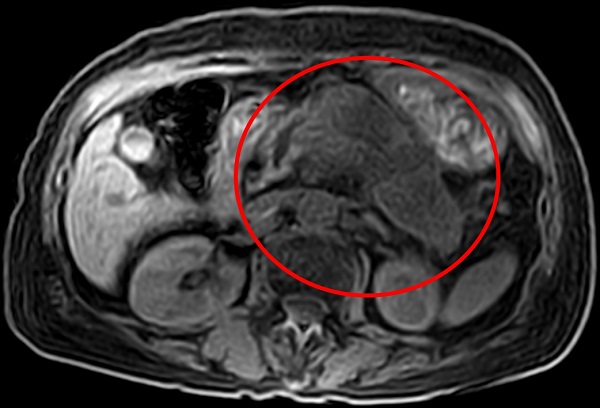

北投健康管理醫院影像醫學部主任沈彥君指出,胰臟位在後腹腔,是身體最中心、最深層的部位,加上位處於胃部後方,即使接受胃鏡及超音波檢查,也多有疏漏,難以提早確診。此外,胰臟癌主要症狀為胃悶、食慾不振,常會與消化系統毛病混淆,不少患者以為腸胃不好,吃了成藥,不僅對於症狀毫無幫助,還延誤就醫,因此,確診時都已到了晚期。

沈彥君進一步解釋,胰臟為細長型,像一條魚橫躺在胃後方,分為胰頭、胰頸、胰體、胰尾等四部分。位在胰臟頭部的腫瘤,容易阻塞總膽管,以致膽汁無法暢流到十二指腸,常有黃疸、食慾不振等症狀;若胰臟癌位在胰尾,在臨床診斷上難度更高,因為腫瘤幾乎不會造成症狀,無聲無息地進展,等到腫瘤大到一定程度或轉移時才會出現體重減輕、食慾不振、腹部不適等症狀。

▲ 胰臟癌症狀為胃悶、食慾不振,常與消化系統毛病混淆,造成延誤就醫。(圖/北投健康管理醫院提供)

沈彥君表示,想要知道胰臟是否健康,必須仰賴磁振造影、電腦斷層,前者無放射線,較為安全,胰臟癌早篩率可達9成;至於超音波檢查,常會被胃腸的空氣擋住視野,成為致命的疏漏。